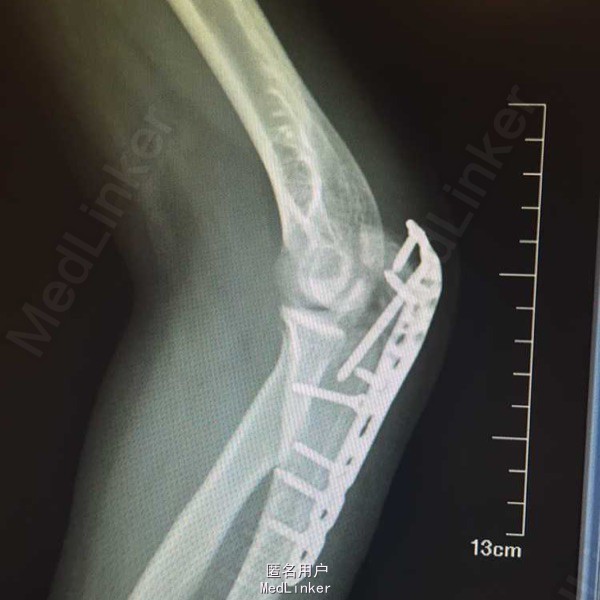

左尺骨鹰嘴粉碎性骨折,专科检查:左肘部肿胀触痛明显,纵向叩击痛阳性,活动受限,左腕部及各指活动正常,末梢感觉正常,桡动脉触动可触及,左上肢肌力、肌张力因疼痛未查。患者因疼痛卧床脊椎未查,左足跟及踝关节肿胀,伴散在丘疹,皮下有瘀血斑,双踝关节主被动活动受限,双下肢肌力,肌张力因疼痛未查。双足足背动脉及胫后动脉搏动正常,双足皮温正常,足趾运动正常。

诊断:1.双侧跟骨粉碎性骨折,2.左尺骨鹰嘴粉碎性骨折3.全身多处软组织损伤。诊疗计划:积极完善入院常规检查及足踝CT三维重建,嘱患者抬高患肢,暂时给予消肿,镇痛等治疗。